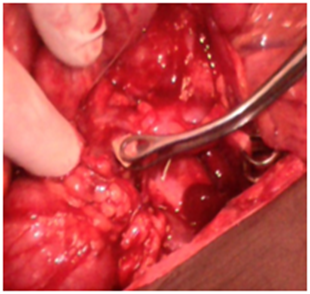

Abdomino-pelvic ultrasound scan revealed an intrauterine viable gestation of 13 weeks with 5 days old as shown in Figure 1A, there was also dilatation of the pelvicalyceal system involving the proximal part of left ureter and presence of 2 calculi within the left renal pelvis, the larger one measured 1.6cm in size as shown in Figure 1B and the right kidney was normal. Serum electrolytes, Urea and Creatinine including urinalysis, urine culture and full blood count were normal. She was then planned and had urethrocystoscopy and Double J stenting of the left ureter under general anaesthesia as shown in Figure 2A. Cystoscopic findings were minimal resistance while stenting the left ureter, which was ultimately, overcame, otherwise normal bladder mucosa and ureteric orifices and no stones within the bladder. Postoperative condition was satisfactory and symptoms subsided. She was later discharged home on oral antibiotics. Since then, she has been regular with her follow up and has been doing well until when she was re-admitted with an assessment of anemia in pregnancy secondary to Malaria and Urinary Tract Infection (UTI) at 32nd week gestation. She responded well to antibiotics and antimalarial, and also had blood transfusion. The serial electrolytes urea and creatinine remained normal. The pregnancy was monitored till term and had spontaneous delivery of normal female neonate weighing 3kg. Patient was re-evaluated in the first week of puerperium, the findings from the repeated abdominal ultrasound scan and KUB were 2 left renal calculi, and one of them has already enlarged to a bigger size of 2.5cm in its widest dimension and presence of intact left ureteric double J stent, otherwise no soft tissue or bony abnormalities seen. She later had left Nephrolithotomy and extraction of double J stent. Intra-operative findings were ‘’stag horn calculus’’ with another small calculus in the left renal pelvis as shown in Figure 2 (B & C). Post-operative condition was satisfactory and was later discharged home. The metabolic evaluation and stone analysis revealed calcium oxalate and calcium phosphate and she was counseled on dietary calcium.

Figure 2(B) Intraoperative calculus extraction.